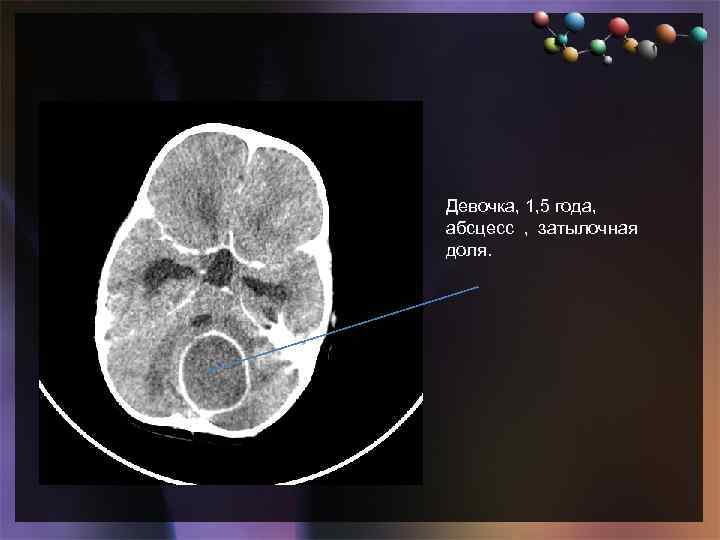

• Подзаголовок слайда Девочка, 1, 5 года, абсцесс , затылочная доля.

• Подзаголовок слайда Девочка, 1, 5 года, абсцесс , затылочная доля.